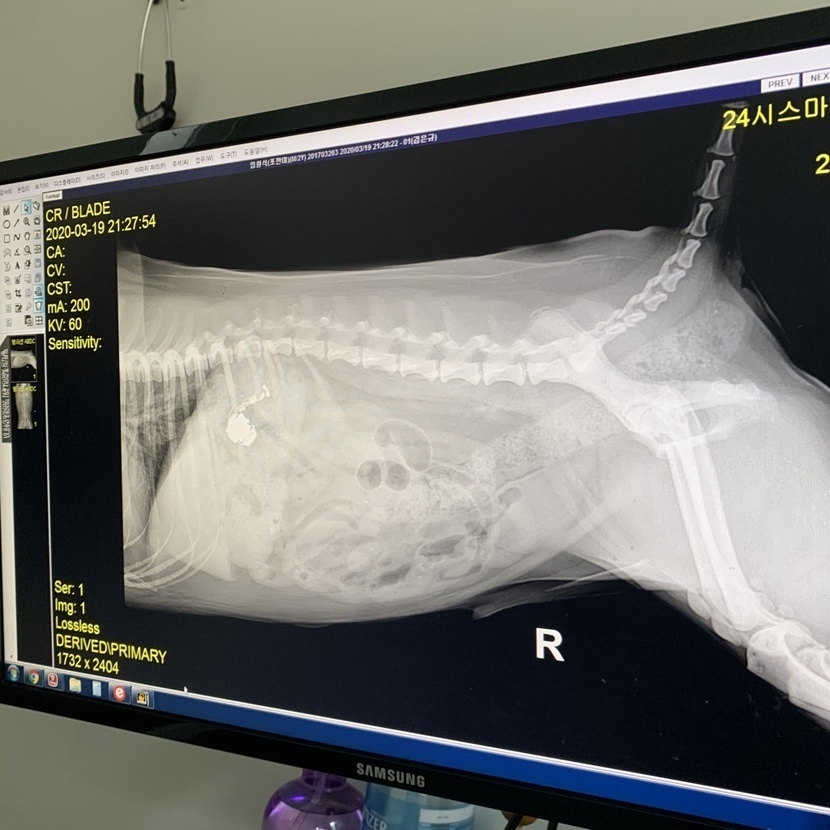

꿀꺽끌꺽 에어팟